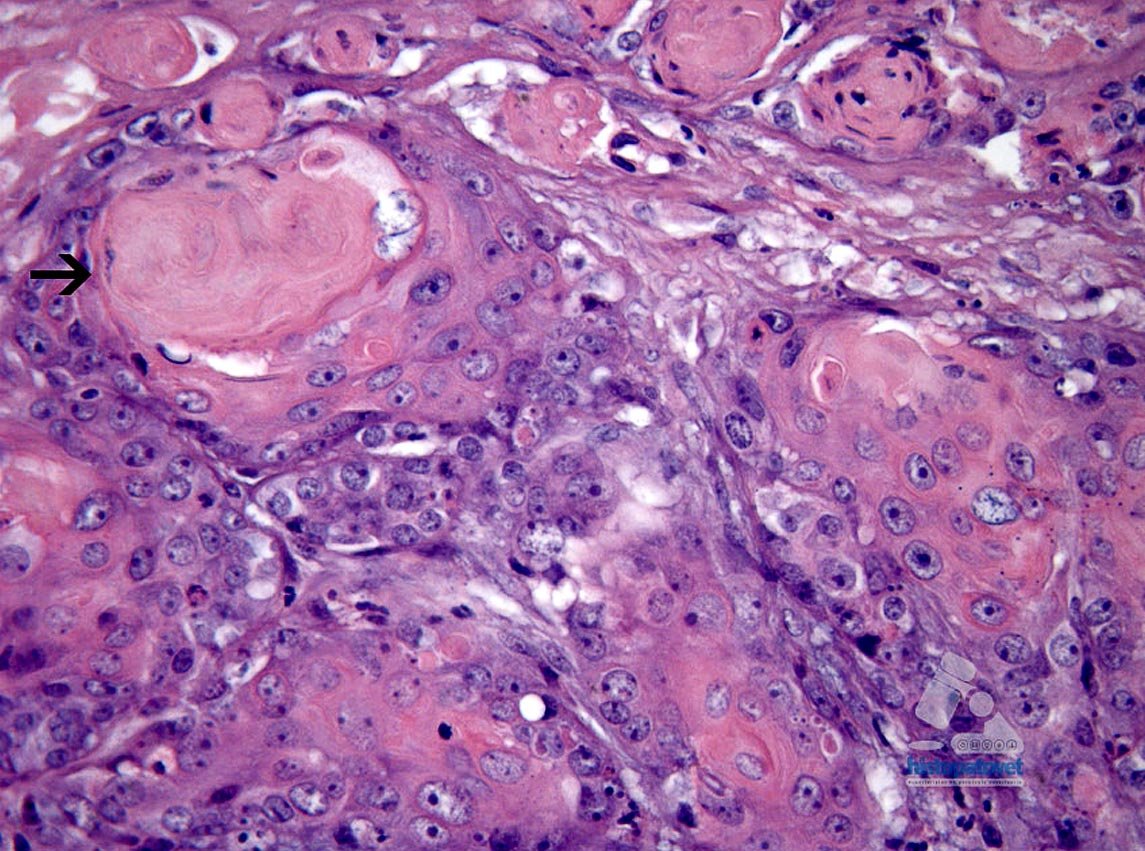

Fig.4. Las flechas indican centros de formación de queratina.El núcleo es redondo-ovalado, pálido, con uno o dos nucléolos. Además, en muchas partes, las células muestran un clara diferenciación a células escamosas( Fig. 5).

Fig.5. Las flechas indican presencia de queratina.